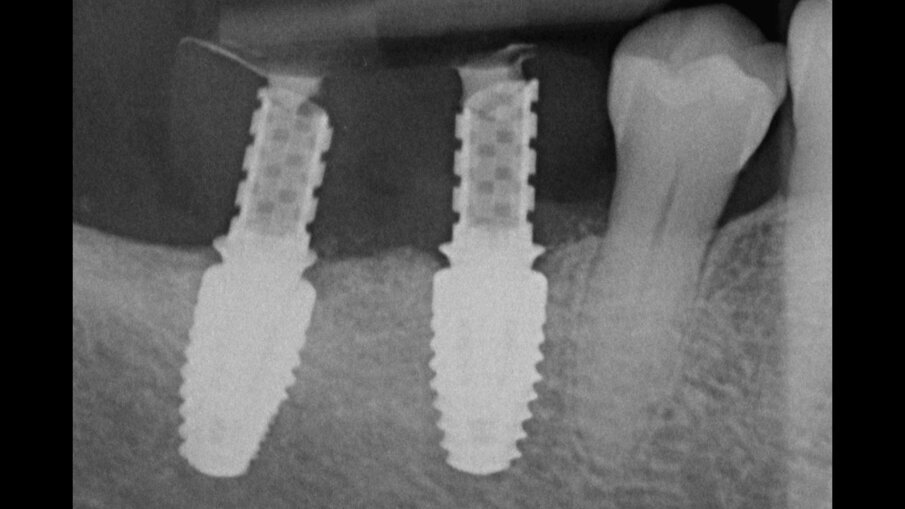

Il prelievo di osso autologo particolato è stato eseguito dal ramo mandibolare, distalmente alla zona da ricostruire mediante uno scraper (SafeScraper Twist, META). La griglia è stata provata nel sito ricevente per verificarne la congruità. Ogni residuo di tessuto connettivo è stato rimosso; per aumentare la rivascolarizzazione precoce del materiale innestato, sono state eseguite delle perforazioni della corticale ossea del sito ricevente (Figg. 3, 4). Dopo preparazione dei siti implantari, sono stati posizionati due impianti “root form” e “bone level” in zona 4.6 e 4.7 (4.1 x 8 mm; Straumann) usando una dima chirurgica. La griglia è stata quindi riempita con un mix di osso autologo ed eterologo (Geistlich Bio-Oss, Gestlich Pharma) in rapporto 1:1, è stata fissata con 3 micro-viti in titanio di 1.4 mm di diametro (MC Bio) ed è stata ricoperta con una membrana riassorbibile (Geistlich Bio-Gide, Gestlich Pharma; Figg. 5, 6). La sutura è stata eseguita per prima intenzione (Fig. 7).

Fig. 5_Visione intra-operatoria della griglia riempita con un mix di osso autologo particolato prelevato dal ramo mandibolare e osso eterologo in rapporto 1:1 e fissata mediante 3 viti in titanio di 1.4 mm di diametro e dopo inserimento di due impianti osteointegrati.